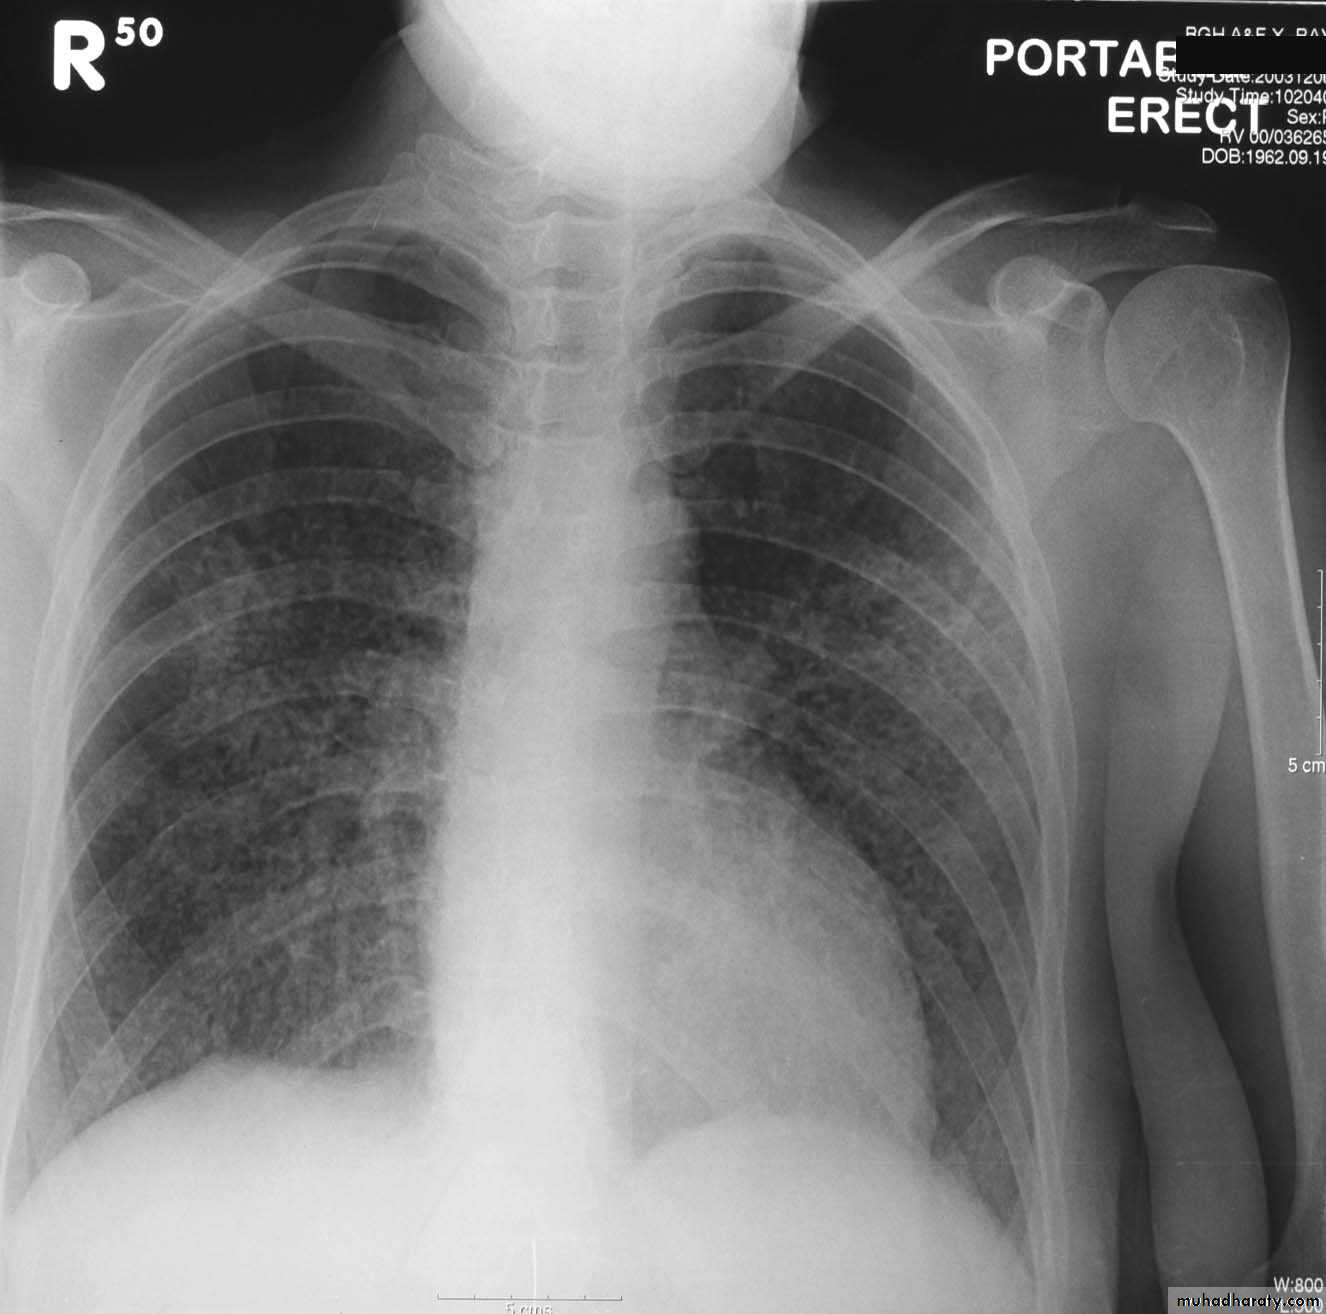

Massive pleural effusion with mediastinal shift to the left.

(A) Chest radiograph(B) CT coronal reconstruction. A massive effusion displaces the mediastinum to the left. CT shows the important pleural effusion together with the enhanced atelectatic left lung.

Note also the depression of the right hemidiaphragm (arrows).